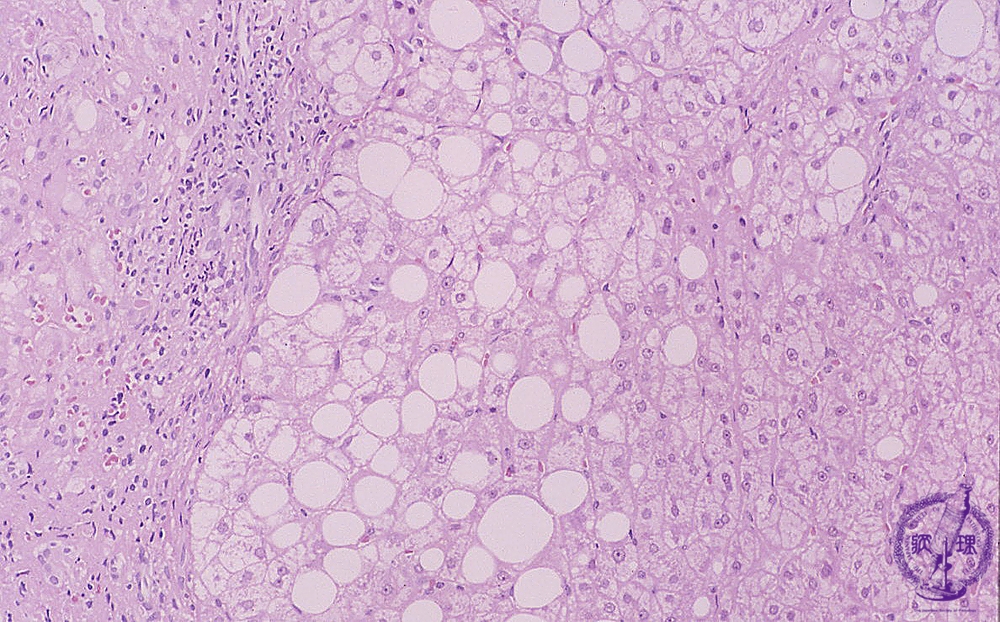

- 10.Liver

- (5)Wilson's disease

Microscopic image (HE stain, intermediate power): Various lesions are observed in the figure. On the left side are infiltrating lymphocytes (yellow circle) and at the center are steatosis and ballooning hepatocytes (red circle). To the right side, there do not appear to be any immediately identifiable abnormalities.

Click the image to see the enlarged image.